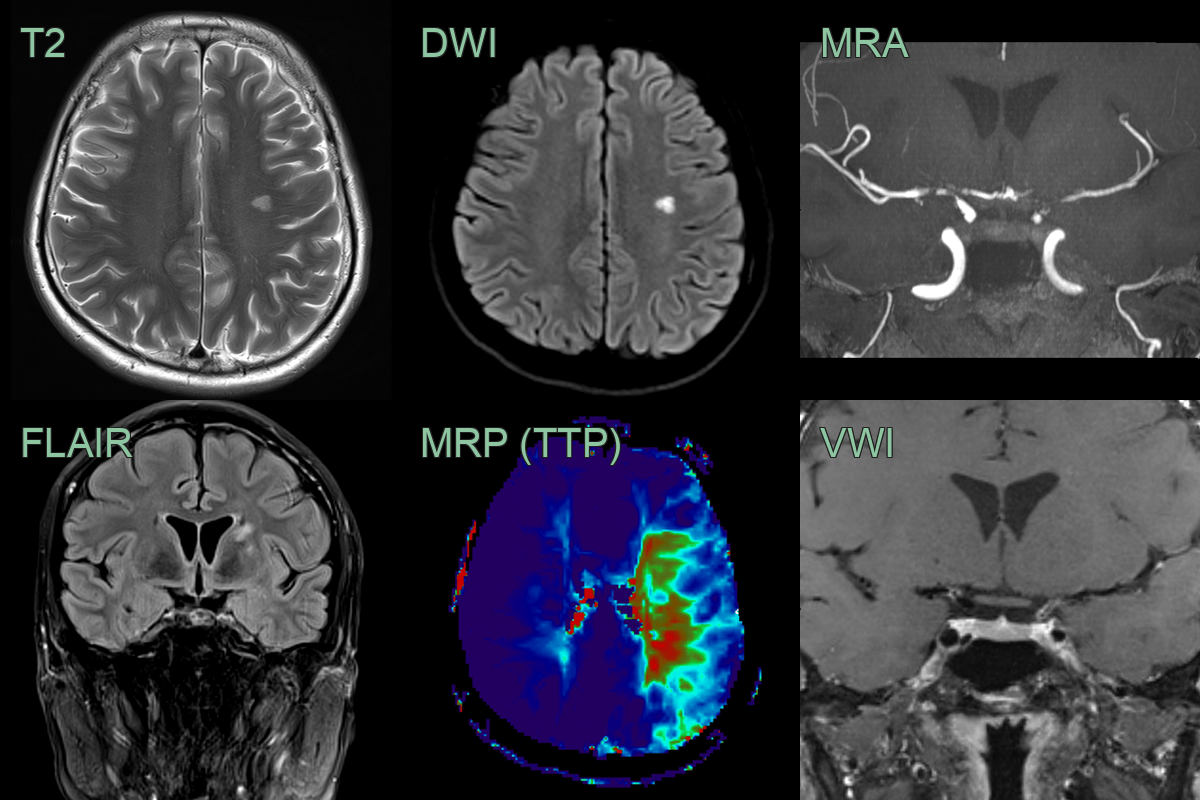

- A 35-year-old patient presenting with photophobia and headache was diagnosed with HIV with a CD40 count of 80.

- Baseline MRI showed an old infarct in the left thalamus. VWI imaging showed concentric enhancement within stenosis in the terminal ICA and MCA.

- Over the following 4-6 weeks, the mural enhancement was static. The stenoses only minimally progressed but the perfusion to the left and, to a lesser extent, right cerebral hemisphere worsened.